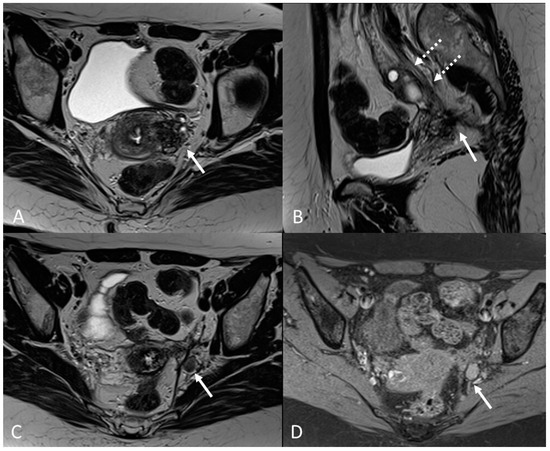

On an MRI, lesions appear as irregular thickness or nodules within the intestinal serosa or muscularis propria, hypointense at T2WI. They rarely affect the submucosa or the mucosa, and if infiltrated, we can observe edema and swelling in the area [7] (Figure 5 and Figure 6).

Figure 5.

External adenomyosis and intestinal endometriosis localization in 49-year-old female with story of multiple laparoscopy surgery. Sagittal T2WI shows a hypointense ill-defined subserosal mass in the posterior myometrium with hyperintense foci (long white arrow), suggestive for external adenomyosis, that cause retracting phenomena towards the anterior wall of the rectum. Additionally, there is deep endometriosis of the posterior compartment with hypointense nodule involving the serous and muscular layers of the anterior wall of the rectum (short white arrow).

Figure 6.

Retrocervical localization, intestinal mushroom cap sign and isthmocele in a 40-years old female. Retrocervical endometriosis localization (white dotted arrow), intestinal “mushroom cap sign” (white arrows) and isthmocele (black arrow).

Generally, they appear hyperintense on fat-suppressed T1WI and T1WI (Figure 7 and Figure 8). The hyperintensity on fat-suppressed T1WI helps differentiate endometriomas from dermoid cyst and teratoma, which usually contain fat [51]. On T2WI, a variable signal can be obtained: a hypointense signal can affect variable portions of the cyst, sometimes also presenting a stratification, until a complete loss of the signal. This is called the shading sign and is correlated to the different state of hemoglobin degradation [52] (Figure 8). The T2 dark spot sign refers to hypointense spots in the wall of the cyst due to the presence of macrophages (Figure 9).

Figure 7.

Ovarian endometrioma in a 37-year-old female. (A) Axial T1WI; (B) Axial fat-suppressed T1WI. Typical aspect of an ovarian endometrioma (white arrows).

Figure 8.

Right tubo-ovarian endometriosis in a 25-year-old female patient with reported localized abdominal pain in the right iliac fossa, which increases intensity during the menstrual cycle. (A) Axial T2WI; (B) Axial fat-suppressed T1WI. Enlarged right adnexal cyst with incomplete septa denoting dilated tube (white arrows). The cystic content shows low signal intensity on T2WI and high signal intensity on fat-suppressed T1WI, consistent with hemorrhagic fluid.

Figure 9.

Diffuse internal and external adenomyosis in a 37-year-old female. (A) Sagittal T2WI; (B) Axial T2WI. Diffuse internal adenomyosis as demonstrated by diffuse hypertrophy of the JZ (white arrowhead in (A,B)), subserosal hypointense ill-defined mass in the posterior myometrium consistent with external adenomyosis (white dotted arrows in (A,B)), with associated deep endometriosis of posterior compartment. Left endometrioma with T2 dark spot sign (white arrow in (B)).